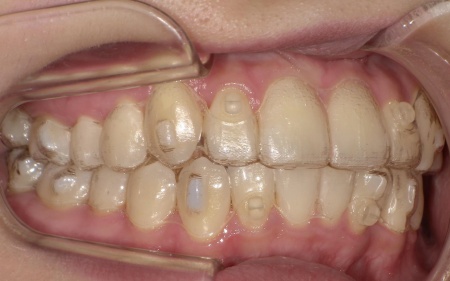

歯並びを改善する方法として、透明なマウスピースを段階的に交換しながら歯を動かしていくインビザラインコンプリヘンシブパッケージによる矯正治療を提案し、同意いただきました。

インビザラインコンプリヘンシブパッケージは装置が透明で目立ちにくく、取り外しができるため食事や歯磨きがしやすい点がメリットです。

マウスピースは定期的に新しいものへ交換しながら、少しずつ歯を移動させています。

治療と並行して、歯と歯の間にスペースを作るためのIPRを適切なタイミングで実施しました。また、噛む力が強い傾向が見られたため、奥歯の噛み込みを抑え、歯をスムーズに動かすために「バイトランプ」と呼ばれる小さな突起をマウスピースの上の前歯の裏側に設置しています。

矯正治療終了後、歯並びの後戻りを防ぐための保定装置を装着していただきました。